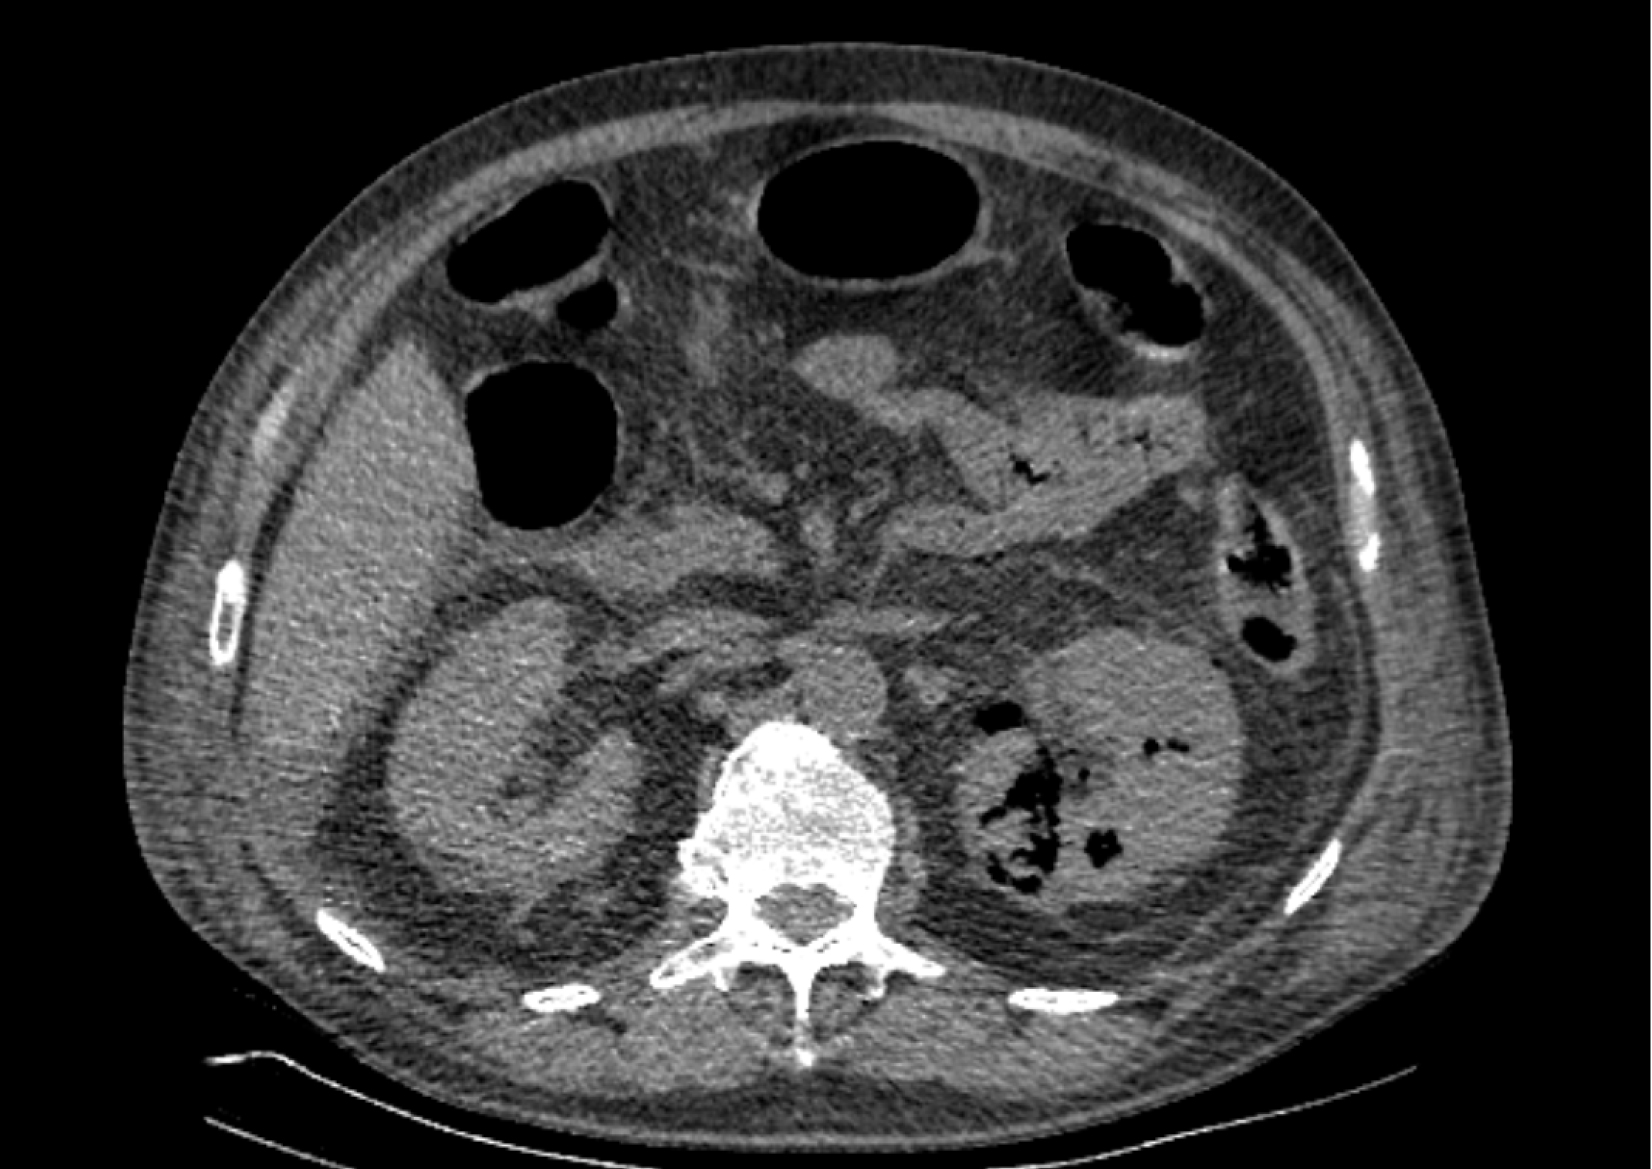

На следующий день состояние пациента оставалось тяжелым, с отрицательной динамикой, креатинин сыворотки возрос до 735,2 ммоль/л, Появились жалобы на слабость, тошноту. При осмотре: живот мягкий, вздут по всем отделам, при пальпации болезненный. Область почек не изменена, при пальпации безболезненна, патологических изменений в области почек не выявлено. Симптом поколачивания отрицательный билатерально. При УЗИ были обнаружены плевральный выпот по 300–400 мл с каждой стороны, гепатомегалия, увеличение размеров селезенки, асцит. Кроме того, в обеих почках были визуализированы тени, характерные для конкрементов. По данным компьютерной томографии (КТ) конкрементов не обнаружено, но в лоханке, на всем протяжении левого мочеточника и, частично, в правом мочеточнике, а также в мочевом пузыре визуализировался газ (рис. 1–6).

Рис. 3. Компьютерная томография органов брюшной полости, забрюшинного пространства, органов малого таза. Газ в левом мочеточнике

Рис. 5. Компьютерная томография органов брюшной полости, забрюшинного пространства, органов малого таза. Газ в левой почке